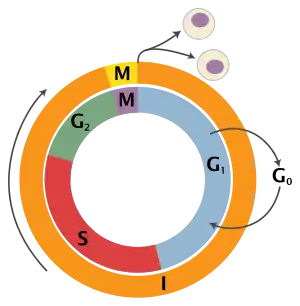

Limitless replicative potential

- Non-cancer cells die after a certain number of divisions. Cancer cells escape this limit and are apparently capable of indefinite growth and division (immortality). But those immortal cells have damaged chromosomes, which can become cancerous.

Cells of the body don't normally have the ability to divide indefinitely. They have a limited number of divisions before the cells become unable to divide (senescence), or die (crisis). The cause of these barriers is primarily due to the DNA at the end of chromosomes, known as telomeres. Telomeric DNA shortens with every cell division, until it becomes so short it activates senescence, so the cell stops dividing. Cancer cells bypass this barrier by manipulating enzymes (telomerase) to increase the length of telomeres. Thus, they can divide indefinitely, without initiating senescence.[4][8]

Mammalian cells have an intrinsic program, the Hayflick limit, that limits their multiplication to about 60–70 doublings, at which point they reach a stage of senescence.

This limit can be overcome by disabling their pRB and p53 tumor suppressor proteins, which allows them to continue doubling until they reach a stage called crisis, with apoptosis, karyotypic disarray, and the occasional (10−7) emergence of an immortalized cell that can double without limit. Most tumor cells are immortalized.

The counting device for cell doublings is the telomere, which decreases in size (loses nucleotides at the ends of chromosomes) during each cell cycle. About 85% of cancers upregulate telomerase to extend their telomeres and the remaining 15% use a method called the Alternative Lengthening of Telomeres.[9]